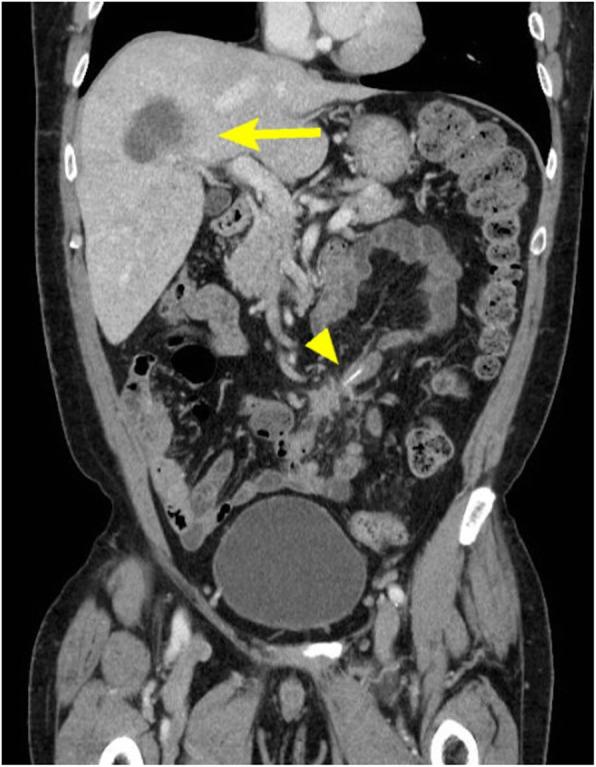

A 54-year-old man visited our hospital because of a fever that had lasted for 1 month. There were no physical findings except for the fever. Laboratory tests showed only elevated inflammatory markers. Abdominal contrast-enhanced computed tomography revealed an abscess in the right lobe of the liver and a high-density object in the small intestine. We diagnosed him with liver abscess secondary to intestinal perforation by a foreign body. The patient underwent drainage of the liver abscess and laparoscopic surgery for perforation of the small intestine. A fish bone had perforated the top of Meckel's diverticulum, which had been covered by the ileal mesentery. We successfully performed diverticulectomy and removed the fish bone. The patient was discharged without complications on the 13th postoperative day.

一名54岁男性因持续发热1个月前来我院就诊。除发热外,无其他体征。实验室检查仅显示炎症指标升高。腹部增强计算机断层扫描显示肝脏右叶有脓肿,小肠内有高密度物体。我们诊断他为异物导致肠穿孔继发肝脓肿。患者接受了肝脓肿引流及小肠穿孔的腹腔镜手术。一根鱼骨穿透了梅克尔憩室顶部,该憩室被回肠系膜覆盖。我们成功进行了憩室切除术并取出了鱼骨。患者术后第13天无并发症出院。